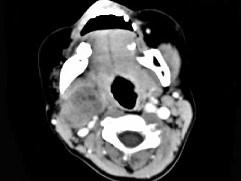

问题 女,4岁,右侧颈部可扪及一包块约两个月,无热无痛,CT如图所示,最可能的诊断为 ( )

选项 A、咽旁神经纤维瘤 B、咽旁小唾液腺混合瘤 C、咽旁副神经节瘤 D、咽旁脓肿 E、咽旁血管外皮瘤

答案 A